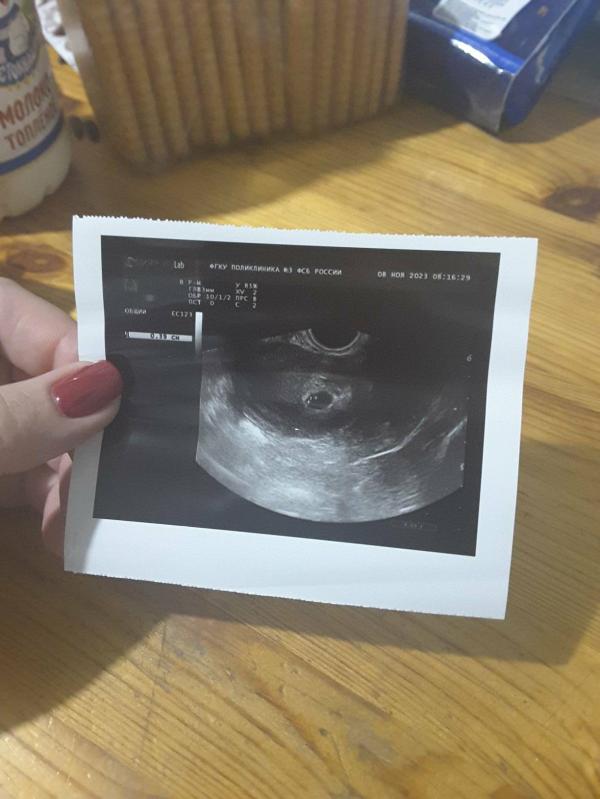

Первое фото😁какие эмоции тогда были, даже не описать, с 20ти лет мне говорили все гинекологи :- Ооо у тебя СПКЯ, очень сложно тебе будет забеременеть, тебе сразу нужно идти в центр планирования, задумайся об эко...

Как видно по значкам, врачи немного ошиблись)

Я до обследований не дошла, записалась я в центр планирвоания но уже не понадобилось) правильно мне эндокринолог подобрала КОКи и на их отмене забеременела, а до этого пила наверно фирм 4, ни как не помогали..